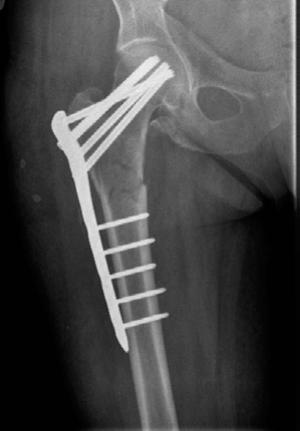

Figure 8.12 Anteroposterior (AP) radiograph demonstrating non-union of the femoral fracture.

Minute 4 EXAMINER : You fixed it with this recon nail. What do you think about your check X-ray? (Figure 8.12.) CANDIDATE : As I mentioned earlier the literature reports better results with the use of a cephalomedullary nail. I hope that when the recon nailing was performed bone grafting to the fracture site was performed as well so as to address both biomechanics and biology. The cephalomedullary nail is in slight varus and there is some translation at the fracture site. The screws in the proximal fragment are a bit superior to where I would normally like them. The screws are not absolutely parallel and I would study my lateral radiographs carefully to make sure that the screws have not missed the head.

Minute 5 EXAMINER : How will you follow-up this patient? CANDIDATE : I would follow-up this patient with clinical reviews and serial radiographs until the fracture heals. I would start her weightbearing as able, stop NSAIDs, counsel against smoking

if she does, keep an eye on her inflammatory markers and do serial radiographs 6 weeks apart. If there is no callus formation at 3–4 months, I would consider revising the intramedullary nail with autologous bone grafting.